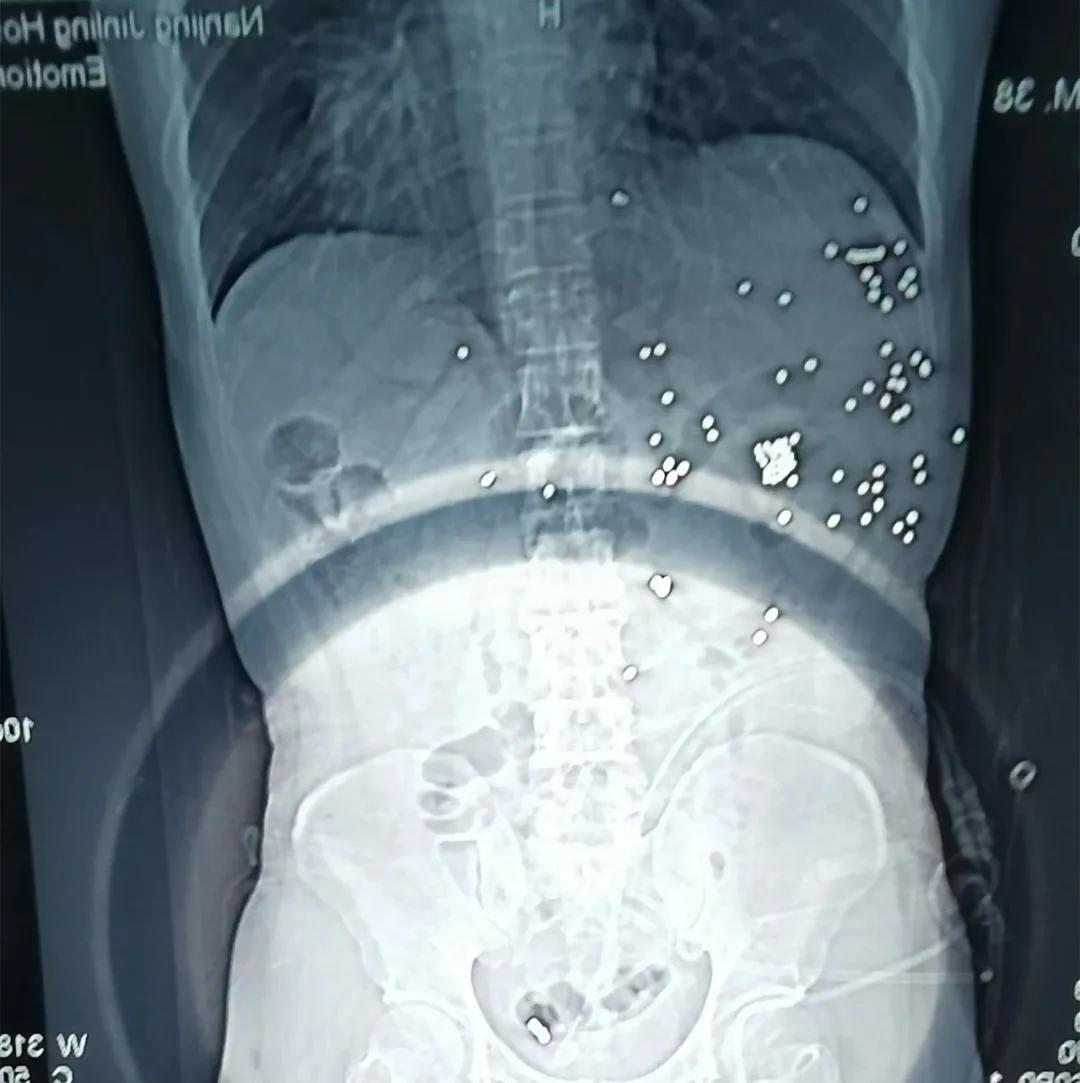

不知,你还记得那张腹腔残留着几十颗*弹霰**铁砂的X光片吗?

还记得那张腹腔残留着几十颗*弹霰**铁砂的X光片吗?片子的“主人”,是台州路桥公安分局的辅警林新志。

于是,一场由肝胆外科、血管、胃肠、创伤外科专家组成的多学科手术在凌晨的手术室里紧张地进行着。打开腹腔后,杨鹏发现林新志的肝部、胃部、胰腺、肠道被*弹子**打伤,近百颗*弹霰**铁砂“侵入”腹腔,在对肝部进行清创后,又是一小时的肝部压迫性止血。探查大血管不再出血后,其他学科团队马上有条不紊地进行手术。当天上午8点30分钟,手术结束。林新志的命暂时保住了,但他体内仍留着近百颗铁砂,胃、小肠、肝脏、胰腺等多个脏器受到重创,血色素也不到常人的三分之一,随时又会陷入危险。

医院全科医学科主任叶宏波,仍记得林新志刚入院时虚弱的样子。院方主要负责对林新志进行全面科学的营养对症支持,为此还特别制定了包含治疗、康复、护理、饮食在内的各种康复方案。经历了4月1日至6月8日、7月2日至8月10日、8月15日至8月28日三个阶段有针对性的康复训练,林新志的体能恢复得不错。每次康复训练提升完,又要去南京进行相关手术或全面检查。只是,那八九十颗残留在体内的*弹霰**铁砂,或将和他度过余生。

从2019年10月2日至今,林新志共经历了6次大手术。每次手术后留下的疤痕,都让人揪心。但乐观的他打趣道,“原来我比较胖,医生告诉我,中弹时,*弹霰**铁砂被打进腹部后,被厚厚的脂肪挡了去路,腹部没有被打穿,所以,胖有时还能在关键时刻救命。”此外,林新志有一个习惯,就是把身份证和银行卡放在左侧衣服口袋,中弹当天,这些卡片也“阻挡”了*弹子**的威力。至今,这些“负伤”的卡片,成了他的“纪念品”。